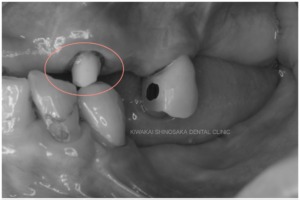

診査・診断の結果、保険内で作製した義歯のプラスチック部分が薄くなっていることと、左上の天然歯1本だけに金具を引っ掛けて支えていたという、非常に不安定な状態のまま義歯を使用されていたため、割れてしまうなどの不具合が頻繁に発生していたことが分かりました。

総義歯を作製するにあたり、複数の残根歯、特に左上に不都合な高さの歯が残っていることが懸念点でした。

(残根歯とは、虫歯や外傷などによって歯の頭の部分が失われ、歯の根だけが歯茎に残っている状態の歯のことをいいます。)

「できれば歯を抜かずに残したい」という患者さまのご意向にお応えし、抜歯は行わず、義歯に影響しないくらいの高さまで調整するだけにとどめた後、上顎用総義歯を作製いたしました。幸い、他の歯や歯周組織に影響を及ぼすほどの虫歯にはなっていなかったため、残根歯は全て抜かずにそのまま残すことができました。